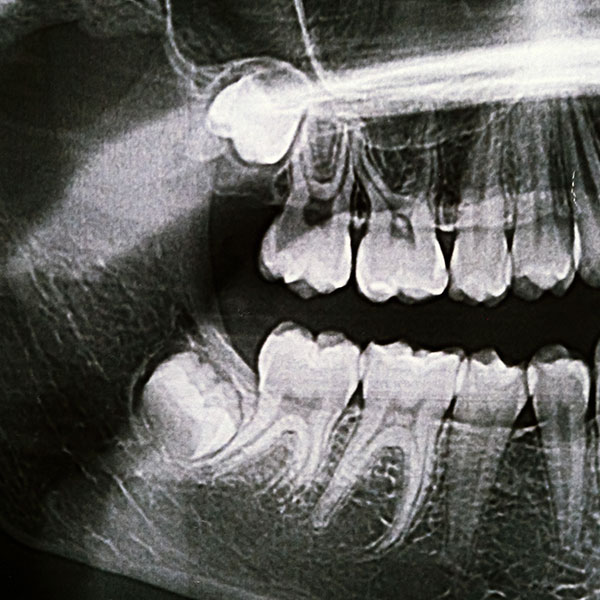

Wisdom teeth often come through on an angle. This can result in them becoming ‘impacted’ or stuck up against the tooth in front.

Impacted wisdom teeth often create a gap between the tooth in front where food gets caught which can create a hole on both the wisdom tooth and the tooth in front of it.

Impacted teeth also often cannot come through fully, and have a little flap of gum at the back which is another place for bacteria and debris to hide.

Decay can develop in both the wisdom tooth and the tooth in front, which may result in the need for both teeth to be removed.